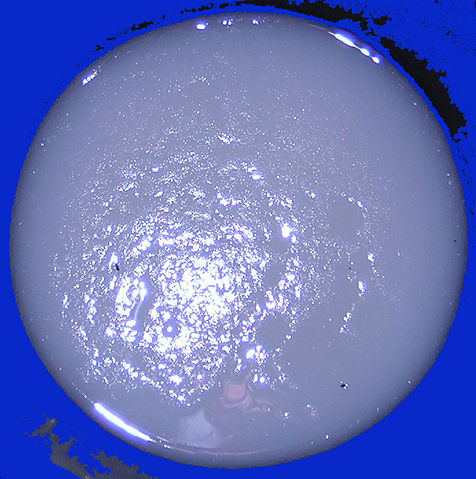

English: Excrement of cholera. Serious patient state

Français : Excrément de choléra incolore et inodore a l'aspect d'eau de riz. Malade en état grave.